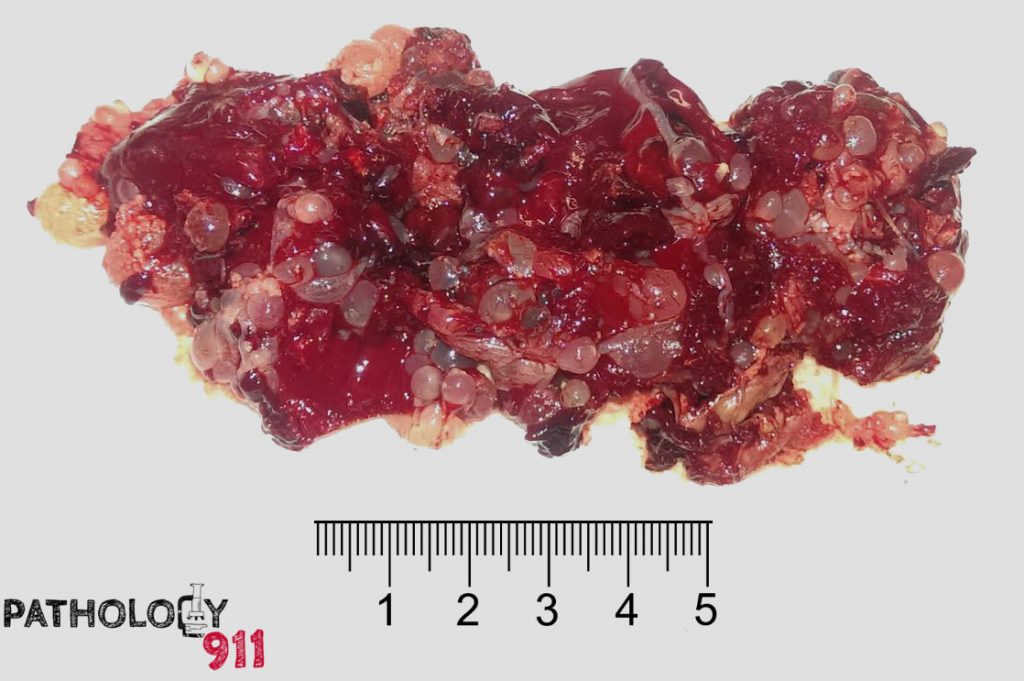

Ruang Praktek Bedah Dokter Ramzi Spb K V Hamil Anggur Pada Kasus Mola Yang Telah Di Kurettage

Ruang Praktek Bedah Dokter Ramzi Spb K V Hamil Anggur Pada Kasus Mola Yang Telah Di Kurettage

Ruang Praktek Bedah Dokter Ramzi Spb K V Hamil Anggur Pada Kasus Mola Yang Telah Di Kurettage

Ruang Praktek Bedah Dokter Ramzi Spb K V Hamil Anggur Pada Kasus Mola Yang Telah Di Kurettage

Ruang Praktek Bedah Dokter Ramzi Spb K V Hamil Anggur Pada Kasus Mola Yang Telah Di Kurettage

Ruang Praktek Bedah Dokter Ramzi Spb K V Hamil Anggur Pada Kasus Mola Yang Telah Di Kurettage